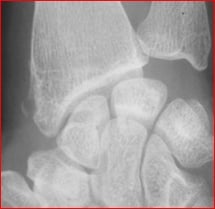

La radiographie du poignet et du pouce est souvent normale.